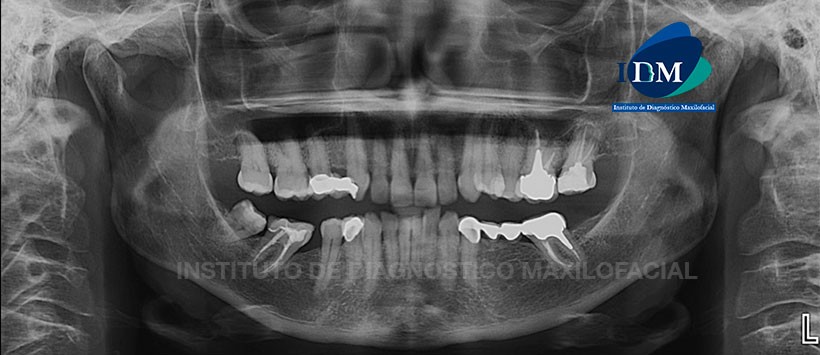

A la evaluación de la radiografía panorámica se visualiza neumatizacion alveolar de ambos senos maxilares, ausencias de piezas dentarias, presencia de pilares de puentes protésicos en las piezas 13, 15, 37 y 34, material de obturación de conductos en las piezas 26, 27, 37 y 47 así como múltiples restauraciones coronarias. Así mismo se evidencia un aplanamiento del contorno de ambos condilos mandibulares y la presencia de una imagen de densidad dentaria proyectada por delante del condilo mandibulares lado izquierdo. (Figura 1)